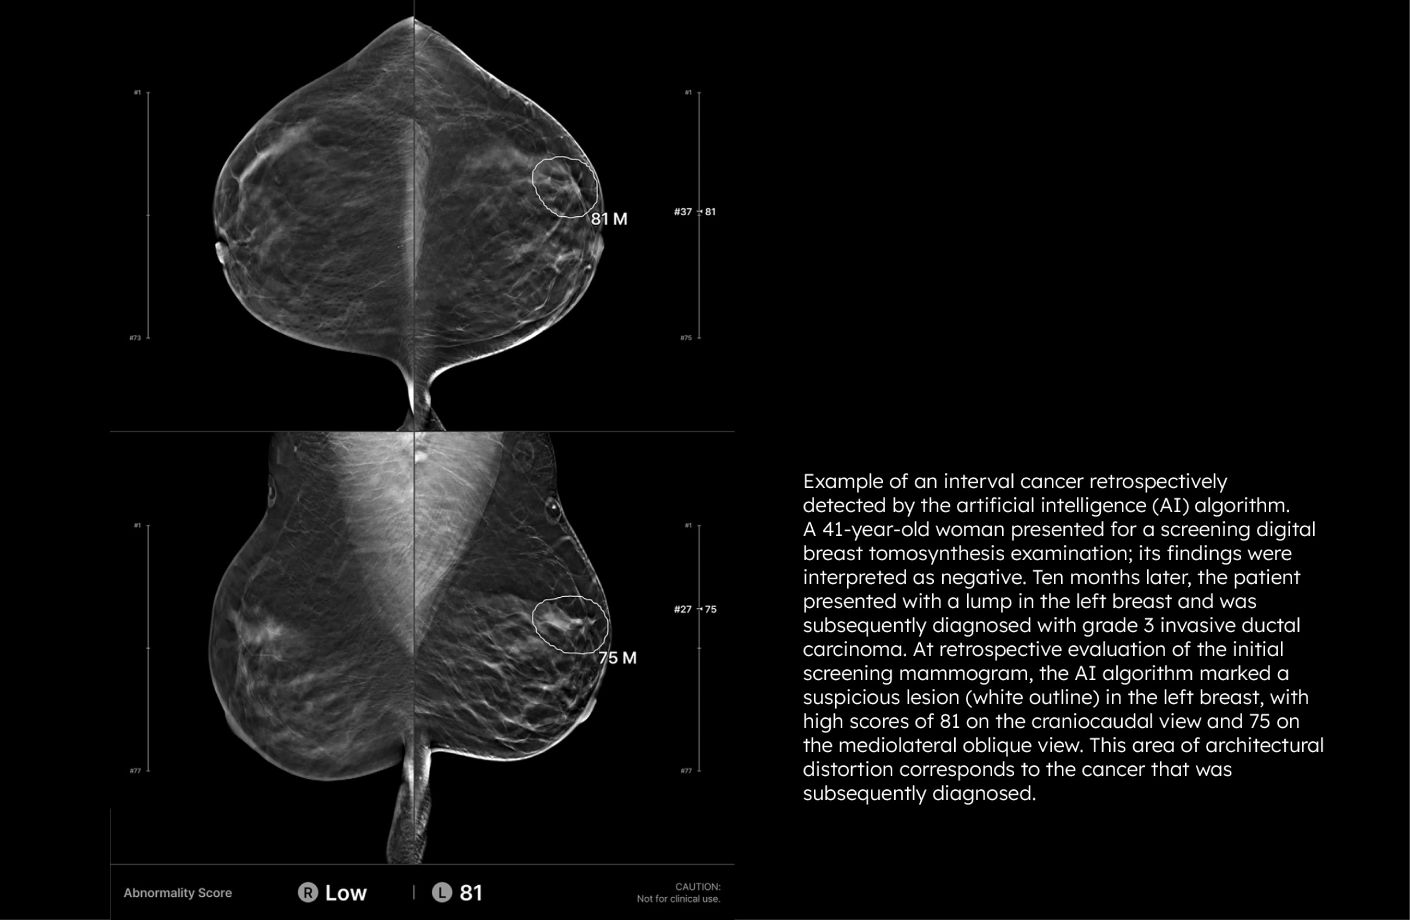

Lunit INSIGHT DBT correctly localized nearly one-third of interval cancers in a recent study*, many of which were large or more advanced. By identifying these earlier, AI can help improve DBT screening outcomes and potentially reduce breast cancer-related mortality and morbidity.

*Bahl M, Langarica S, Lamb LR, et al. AI to Reduce the Interval Cancer Rate of Screening Digital Breast Tomosynthesis. Radiology. 2025

Each suspicious lesion is assigned an abnormality score (0–100), helping quantify malignancy likelihood. Location is clearly marked using heatmaps or contours, and lesion types—such as masses (including architectural distortion and asymmetry), and calcifications—are identified for targeted interpretation. The best slice for lesion visualization is marked on the navigation bar for quick review.